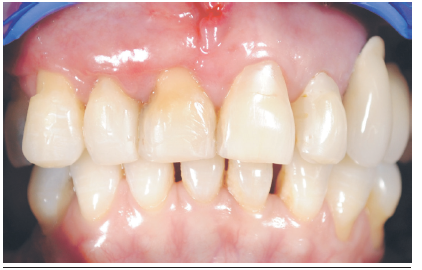

Se presenta el caso clínico de una paciente sana género femenino de 60 años. Sin antecedentes de alergias ni consumo de tabaco. Al examen clínico se evidencia una extensa recesión RT1 de Cairo11 clase B -12 en relación al diente 1.1 de 6 mm, el cual presentaba una restauración cervical con composite y movilidad tipo 1. Figura 2. Al examen imagenológico se evidencia una pérdida total de la tabla vestibular y una parte del hueso en relación al ápice de diente. Figura 3. La indicación inicial fue la regeneración ósea y la planificación de un implante. No obstante, la falta de tejido blando y duro en vestibular, hicieron que fuera estéticamente imposible, ya que correspondía a una clase 3 de Elian por lo que no fue posible realizar una técnica de “Ice cream cone”1 y/o la instalación del implante simultáneamente2. Por lo que fue necesario regenerar primero el tejido blando y transformar de una clase 3 a una clase 2. Figura 4.

En este caso se planificó resolver la recesión del diente 1.1, mediante una técnica de colgajo desplazado lateral e injerto de tejido conjuntivo subepitelial. Figura 5.